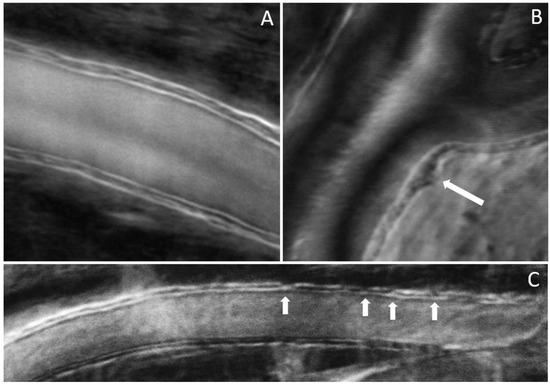

The results shown in Figure 4, Figure 5 and Figure 6 were obtained from a healthy subject. Figure 7, Figure 8 and Figure 9 show images obtained from eyes with different levels of DR severity. Figure 7A is from the same control as in Figure 4, Figure 5 and Figure 6. Figure 7B,C are from two subjects with T1D but no DR. Figure 8A,B correspond to subjects with mild nonproliferative DR (NPDR), C is from a moderate NPDR subject, D is from a severe NPDR subject, and E/F is from a proliferative DR (PDR) subject. All images in Figure 7 and Figure 8 are MPG except for Figure 8F, which is the STD image corresponding to Figure 8E. Similarly to Figure 6, Figure 9A shows the vessel diameter (VD—magenta) and lumen diameter (LD—green) as a function of position along the vessel for a scan partially shown in Figure 8C, and Figure 9B displays the WLR.

Figure 7.

(A) Control; (B,C) no DR; arrows indicate disruption of the wall integrity.

Figure 8.

(A,B) Mild NPDR; (C) moderate NPDR; (D) severe NPDR; (E,F) PDR; arrows in (A,B) indicate disruption of the wall integrity; arrow in (D) indicates a microaneurysm.

The imaging method and the analysis procedure presented here enable the identification of structural abnormalities that are the result of disease, DR due to T1D in particular in this study. Loss of structural integrity of the blood vessel wall may result in MAs, a hallmark lesion of DR, which may leak or rupture and further cause visual decline. Figure 7 and Figure 8 show several examples of structural distortions in subjects with various levels of DR severity. The healthy eye illustrated in Figure 7A has strong continuous vessel borders. In contrast, the rest of the images in Figure 7 and Figure 8 show disruptions in the vessel walls, indicated by the arrows, either bulging or local thinning of walls that may become the location of future MAs like the one shown in Figure 8D (arrow). Additional videos (Videos S2 and S3) and an image (Figure S1) are included in the Supplementary Materials to illustrate very faint blood flow through the MA, which is confirmed in the STD image by the very dim motion contrast bulge next to the blood vessel. Figure 8E,F show significant variations in the lumen diameter in a portion of the vessel that has no additional branches (white oval) for a PDR subject. It is expected that the lumen diameter changes across a branch for flow conservation while it should be relatively constant in between branches. DR might affect the elasticity/stiffness of the vessel wall, and distortions could occur, such as those illustrated here. Similarly, Figure 9 shows tremendous variations in the lumen and vessel diameters along a vessel of an eye with moderate NPDR. It seems that the wall thickness is relatively constant while the lumen/vessel diameter varies significantly (also arrows in Figure 8C). The result is a large variation in WLR along the vessel, as shown in Figure 9B, in between branches. Future prospective studies may elucidate whether increased variation in WLR is associated with future problems related to vessel wall integrity.